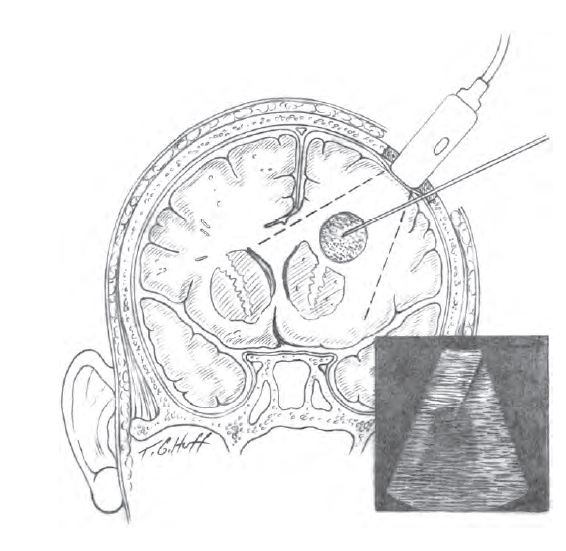

Основним методом хірургічного лікування є дренування гнійного вогнища: після ретельного планування оперативного втручання, пацієнту під загальним знеболенням виконується пункція скупчення гною, після чого в порожнину встановлюється дренажна припливно-відтічна система.

Через неї протягом кількох днів відбувається відмивання залишків гнійного вмісту розчинами антисептиків і антибіотиків. В ході операції вміст абсцесу або емпієми береться для аналізу з метою вибору найбільш ефективного антибіотика.

Однією з останніх методик, впроваджених в нейрохірургічному відділенні, є дренування гнійних процесів головного мозку під ультразвуковою навігацією, що підвищує її точність і зменшує травматизацію здорових тканин.